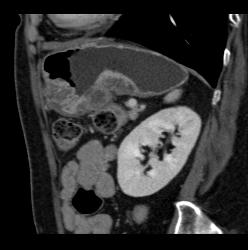

Antral Carcinoma With Adenopathy